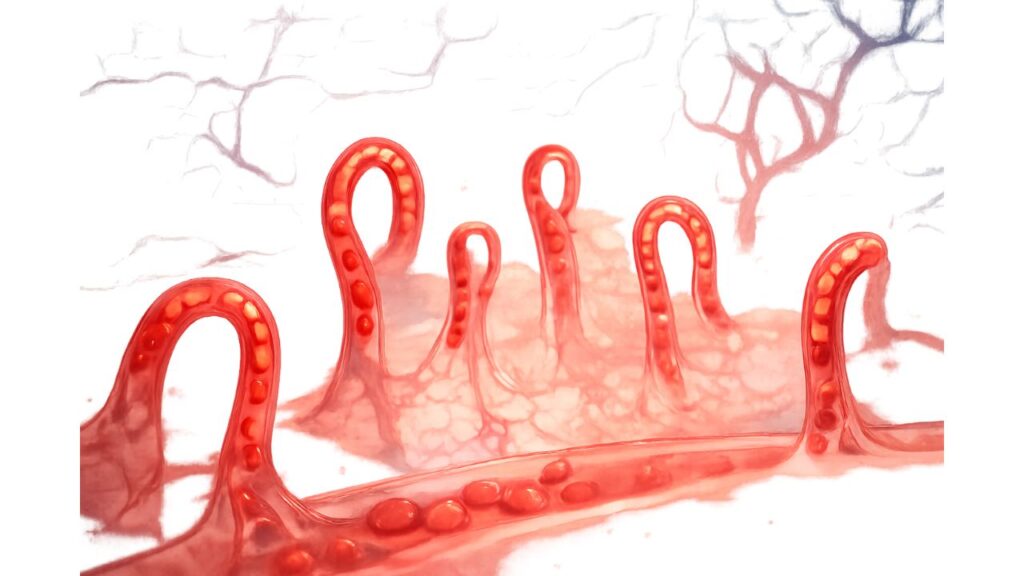

毛細血管の機能低下→「巡らない・漏れる・炎症」

毛細血管は壁が薄く影響を受けやすい分、状態が乱れると

- 栄養の届きにくさ

- 老廃物の滞り

- 炎症が起こりやすい状態

につながる可能性があると考えられています。

毛細血管は変化が出やすい(だから観察に向く)

動脈が三層構造なのに対し、毛細血管は単層の内皮細胞を主体とするため、血流・自律神経・生活習慣の影響が“末端に現れやすい”とされます。

理想は「まっすぐなヘアピン状+規則正しい並び」

- まっすぐ伸びたヘアピン状

- 太すぎず細すぎず、均一

- 規則正しく並ぶ

こうした状態は「流れがスムーズに見える」ことが多いとされます。